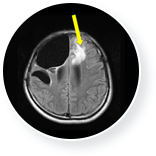

GC녹십자아이메드의 뇌종양 치료 사례로, 36세 남성 환자가 초진 시 악성 뇌종양(교모세포종, glioblastoma) 진단을 받은 후,

뇌종양 전체 절개와 항암화학치료, 방사선 치료를 실시했습니다. 치료 이후에도 뇌종양이 재발하여, 면역세포치료를 16회간

시행하였습니다. 뇌 CT 검사결과, 뇌종양 크기가 감소 및 진행이 멈추면서 재발되지 않게 되었습니다.

• 뇌종양 치료 전 이미지

뇌종양 치료 전